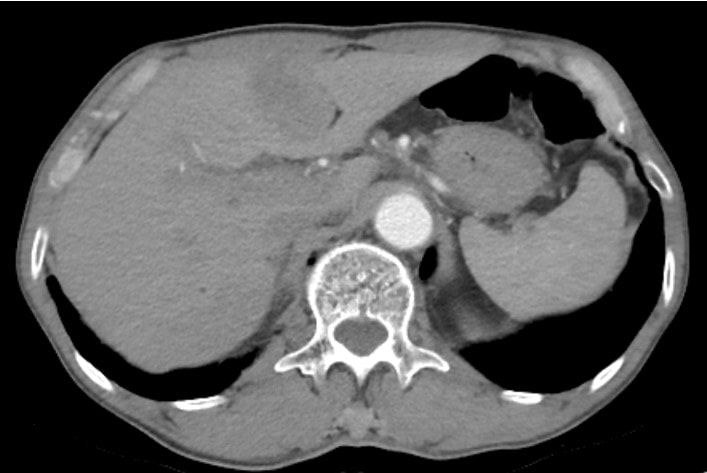

Sỏi mật có thể gây ung thư nếu không được điều trị sớm

(CLO) Viên sỏi đường mật thường được nhiều người bỏ qua, đôi khi lại là mầm mống của một căn bệnh ung thư nguy hiểm. Đây không chỉ là một bệnh lý hiếm gặp mà còn là một thách thức lớn trong y học do khó chẩn đoán sớm và điều trị phức tạp.

Lấy hàng trăm viên sỏi trong bụng người phụ nữ bị sỏi mật

(CLO) Bệnh viện Đa khoa khu vực Cẩm Phả vừa phẫu thuật thành công cho người phụ nữ bị túi mật hai ngăn hiếm gặp, hàng trăm viêm sỏi được lấy ra từ bụng bệnh nhân.